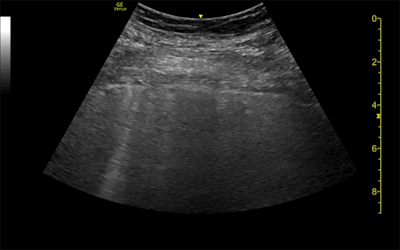

Ultrasound and CT images from a 62-year-old woman with long-term COVID-19 symptoms. The patient, who was not part of the study, visited the Madrid emergency department with persistent dyspnea and cough. The ultrasound image (above) shows an irregular pleural line and some B-lines, which correlate to ground-glass opacities in the lower lobes on CT (below). Images courtesy of Dr. Yale Tung-Chen, PhD.

The patients underwent both lung ultrasound and chest CT scans, which revealed a variety of abnormalities related to COVID-19:

- The 35-year-old woman had a mild, irregular pleural line and B-lines in her right anterior chest on ultrasound, which correlated with ground-glass opacities on CT.

- The 41-year-old woman had an irregular pleural line in her right lateral area on ultrasound, which correlated with pleural thickening on CT.

- The 64-year-old man had a marked, irregular pleural line and multiple B-lines on ultrasound, which correlated with fibrotic changes on CT.